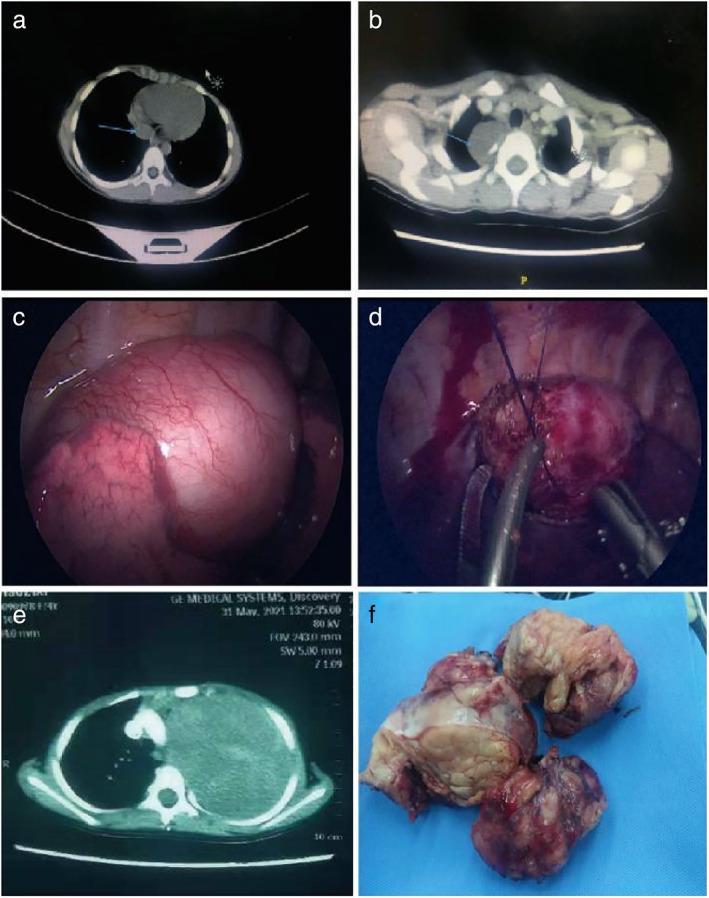

To study the feasibility, safety, and efficacy of thoracoscopic surgery in the treatment of pediatric mediastinal neurogenic tumors, and summarize the treatment experiences and surgical skills.

A single-center retrospective analysis of 37 patients with pediatric mediastinal neurogenic tumors was conducted. Clinical charactersistics and postoperative complications were all analyzed.

All the operations were successfully completed. There was no statistically significant difference in tumor diameter between the two groups (p > 0.05). The open surgery group had an average operation time of 96.5 ± 32.38 min, while the thoracoscopic surgery group had an average operation time of 78.3 ± 24.51 min (p < 0.05). The thoracoscopic surgery group had significantly lower intraoperative blood loss than the open surgery group (p < 0.05). In addition, the duration of the postoperative thoracic drainage tube was 5.43 ± 0.76 days in the open surgery group, which was longer than the 2.38 ± 0.87 days in the thoracoscopic surgery group (p < 0.05). Furthermore, the postoperative length of hospital stay was an average of 10.23 ± 1.43 days for the open surgery group, longer than for the thoracoscopic surgery group (4.36 ± 0.87 days) (p < 0.05).

Thoracoscopic surgery has several advantages in the treatment of pediatric mediastinal neurogenic tumors and is worthy of clinical popularization and application. For giant mediastinal malignant neurogenic tumors, puncture biopsy and adjuvant chemotherapy can be performed before surgery to lessen the tumor volume and enlarge the operation space, which would reduce bleeding and complications.